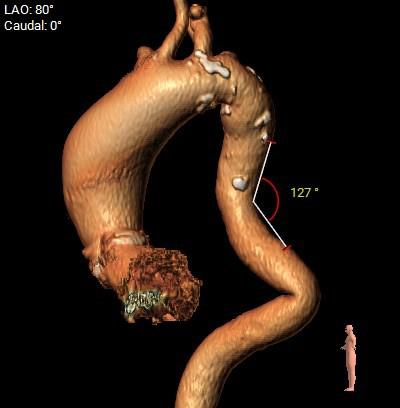

瓣环角度及弓角弓距

◇ 主动脉瓣环水平夹角52°,非横位心,主动脉弓角度较锐(43°)及弓距偏短;

◇ 外周入路血管走形迂曲,降主动脉有较锐夹角,主动脉弓,降主动脉,胸主动脉,腹主动脉有附壁钙化分布,血管内径可。